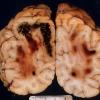

MYELIN (IMMUNE-MEDIATED)

AHL

AHL (3)